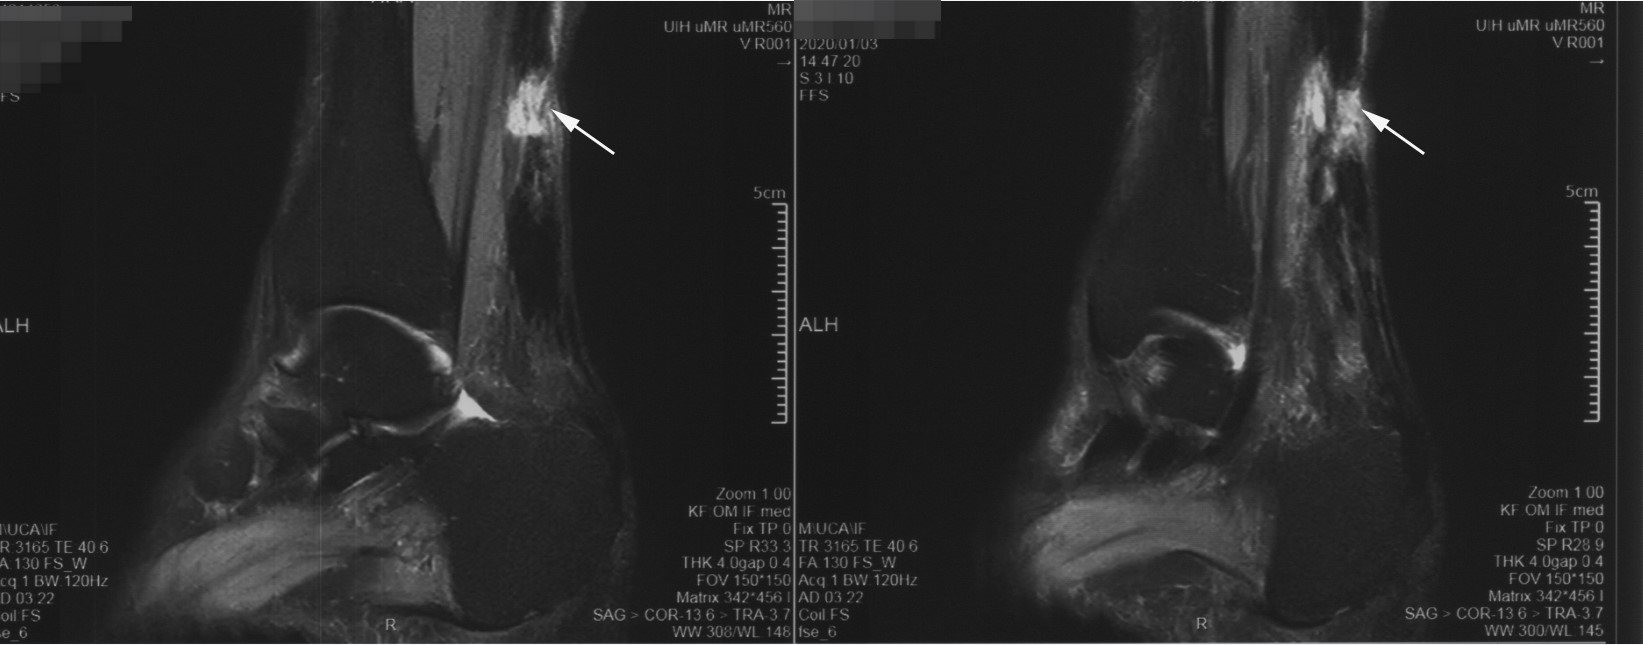

56岁的杨阿姨,平常喜欢跳跳广场舞,运动量并不是很大。一次跳舞时,听到砰的一声,感觉右脚后脚跟像被人踩了一脚,还有明显的疼痛,靠近脚跟的地方还有一块空空的感觉。找社区的门诊医生看了看,贴膏药、红花油用了2个多月,症状却不见好。于是来看了我的门诊。经过查体,我发现踝关节Thompson征阳性,建议他做踝关节核磁共振,报告结果示右侧跟腱断裂。杨阿姨已经经历了一个月的脚痛折磨,对以后运动、跳舞的要求也比较高,因此得知确诊跟腱断裂后,就积极接受了手术治疗。故门诊以“右侧陈旧性跟腱断裂”收入院。(图1)

图2 术前核磁共振显示跟腱陈旧性断裂